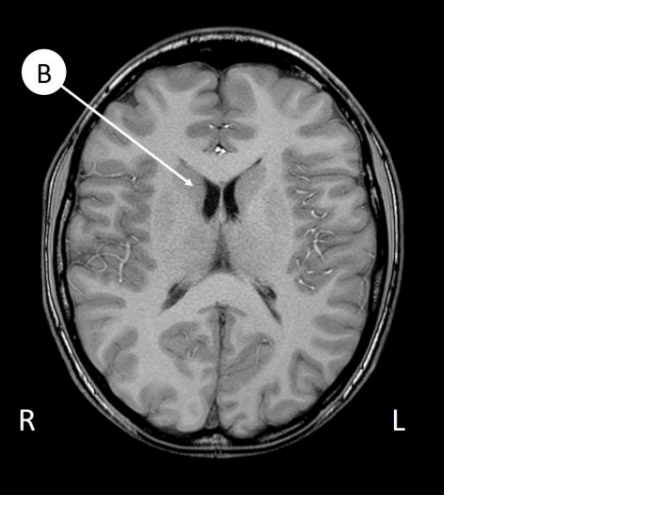

ventriculus lateralis dex.

Thalamus Dex.

nucleus lentiformis dex.

capsula interna sin.

septum pellucidum

nucleus caudatus dex.

ventriculus III